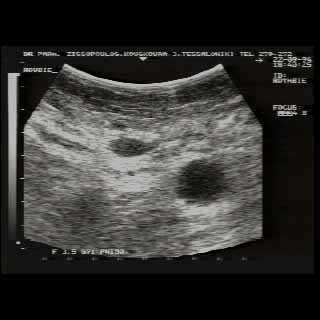

Οι απεικονίσεις των περιστατικών που επιδεικνύονται παρακάτω, έγιναν με κυρτές κεφαλές 3,5 και 5 ΜΗΖ, προκειμένου να φανεί, ότι και με τον εξοπλισμό αυτό, που σιγά-σιγά διαθέτουν όλο και περισσότερα ιατρεία, είμαστε σε θέση να έχουμε ικανοποιητικά αποτελέσματα.

Oι τελευταίες 4 απεικονίσεις έγιναν με ειδικό για μαστό ηχοβολέα linear, εναλλασσομένης συχνότητος 7,5-10ΜΗΖ.